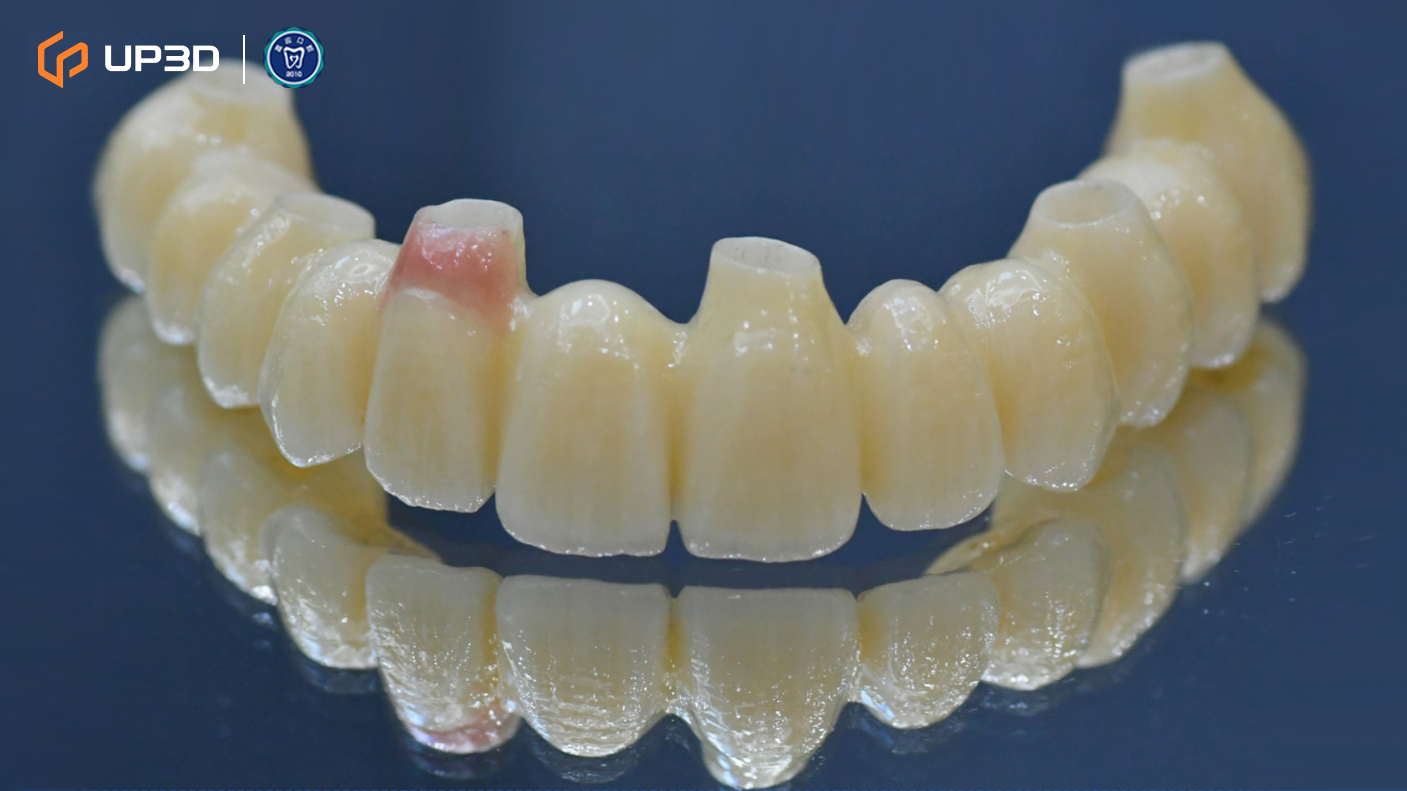

7.3 Chairside Milling of the Zirconia Restoration

High-strength zirconia was selected for chairside fabrication. Milling was performed using the UP3D P55D. The definitive restorations showed:

-

Clean, well-defined margins that supported accurate seating

Stable surface quality and consistent milling results

High fidelity in anatomical morphology and occlusal detail reproduction—helping reduce chairside adjustments and minimizing the risk of remakes

The zirconia restorations were completed within approximately 48 hours, enabling a timely transition into final delivery.

7.4 Final Delivery

After delivery, the definitive prosthesis demonstrated:

Balanced occlusal contacts and an esthetically pleasing profile

Appropriate hygiene access and comfortable function